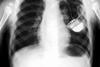

Hospitals must update 100,000 pacemakers after safety fault

Hospitals are having to update more than 100,000 patients’ pacemakers – and replace hundreds of the devices – after the manufacturer discovered their batteries run down years early, HSJ has learned.